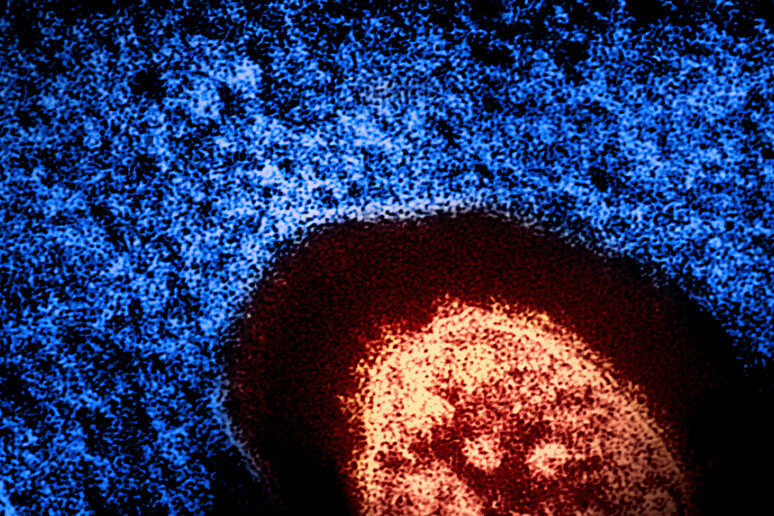

Beata Halassy decidió atacar su tumor con dos virus secuenciales: un virus del sarampión y un virus de la estomatitis vesicular (VSV). Ambos han mostrado potencial en ensayos clínicos y, según Halassy, ofrecían un historial de seguridad aceptable. El virus del sarampión utilizado era de la misma cepa empleada en vacunas infantiles, mientras que el VSV genera, en el peor de los casos, síntomas similares a los de una gripe leve.

Con la ayuda de un colega, Halassy preparó material de grado de investigación en su laboratorio y recibió inyecciones directamente en el tumor durante dos meses. Los oncólogos supervisaron de cerca su progreso, listos para intervenir con tratamientos convencionales si surgían complicaciones.

Sin embargo, el enfoque experimental funcionó. El tumor comenzó a reducirse, se ablandó y se separó del tejido muscular y cutáneo circundante, lo que permitió una cirugía más sencilla y efectiva.

Tras la extirpación quirúrgica, los análisis revelaron que el tumor estaba completamente infiltrado por linfocitos, células inmunológicas que indican una respuesta activa del sistema inmunológico contra el cáncer y los virus. Halassy atribuye este resultado a la eficacia de la viroterapia, afirmando: “Se produjo una respuesta inmunitaria, sin duda”.